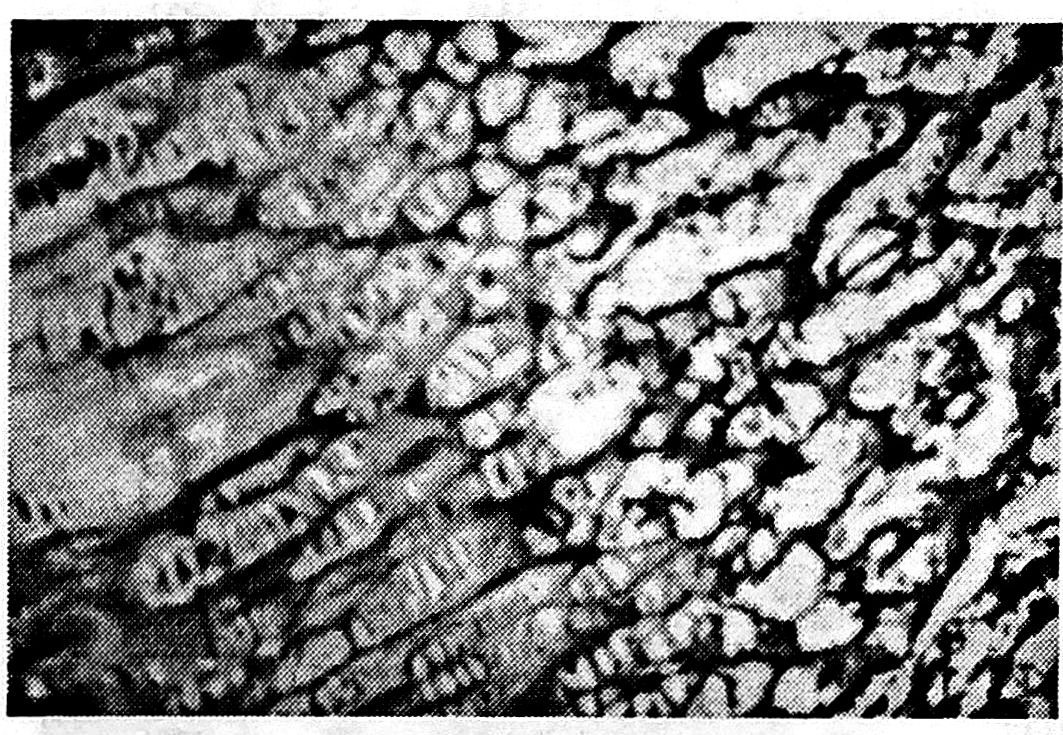

Результаты и обсуждение. В основной серии опытов через 42 дня после травмы на гистотопограммах определялась зона роста без видимых изменений (рис. 2). На гистограммах в большинстве случаев выявлялась эпифизарная хрящевая пластинка со всеми присущими ей слоями. Сохранялись правильные соотношения пролиферирующего, созревающего и обызвествленного слоев с наличием в них бесклеточных участков дистрофии. Наряду с этими участками отмечалось большое количество «колонок» (зон пролиферации и созревания). Наблюдалось активное костеобразование в зоне обызвествления и субхондральной кости метафиза (рис. 3). Диастаз между отломками заполнялся молодой ретикулярной тканью.

Рис. 2. Гистотопограмма ростковой зоны дистального отдела бедра на 42-й день после травмы и проведения одномоментной дистракции на 1,5 мм с жесткой фиксацией в аппарате (I серия опытов).

Рис. 3. Гистограмма зоны роста на 42-й день после травмы и проведения дистракции на 2 мм с жесткой фиксацией в аппарате (I серия опытов).

Окраска гематоксилином и эозином. Ув. 120.